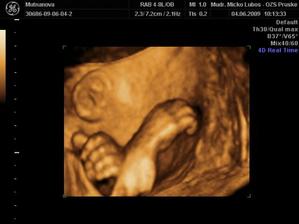

Naše druhé zlatíčko